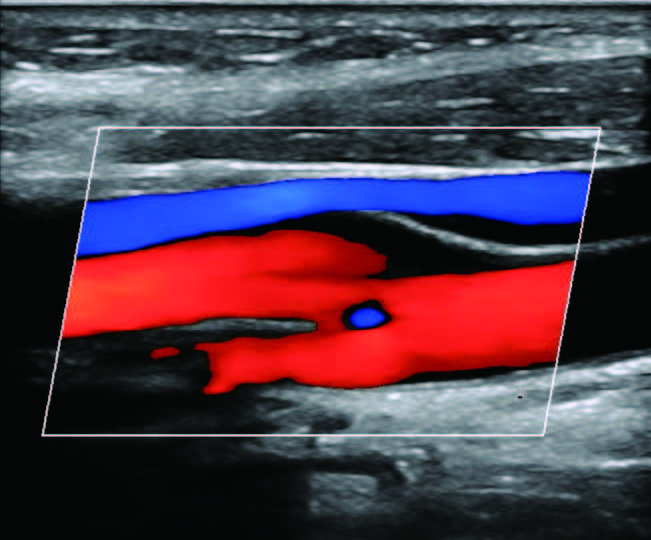

На изображениях, приведенных ниже показаны примеры из клинической практики врачей ультразвуковой диагностики, полученные в процессе апробирования прибора Mindray Resona 7. Приводится наглядные примеры сравнения традиционного режима ЦДК и режима V Flow (Vector Flow).

Изображена яремная вена и бифуркация сонной артерии. CAA, ICA и ECA показаны на одном изображении. В режиме ЦДК отсутствует подробная гемодинамика. В режиме V Flow отображаются данные о скорости и направлении движения частиц крови во всей зоны интереса, включая изменения характеристик кровотока в сонной артерии и яремной вене.